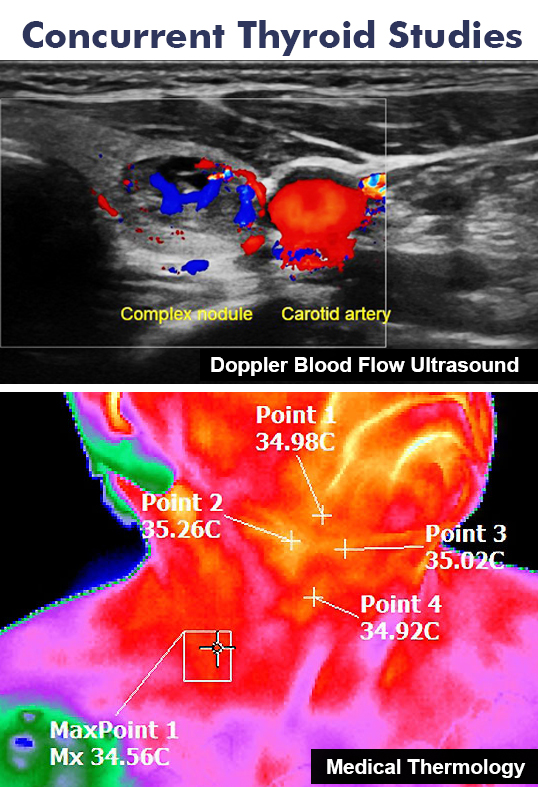

Employing state-of-the-art processing technology, our partners at Therma-Scan Labs work closely with our technicians to gather the most compelling data from each bioscan as part of quantitative analysis to screen and accurately report on pathologies- which can also be applied in early detection. Most commonly applied for the earliest indication of breast cancer, Thermology is also recognized for its utility in the detection and screening of:

- carotid and thyroid disorders